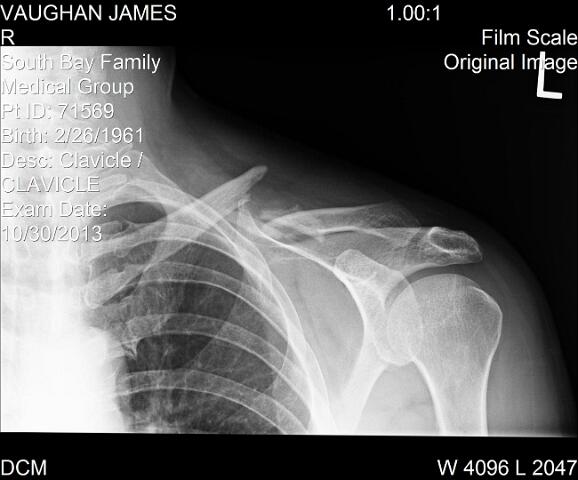

Clavicle

© Jim Vaughan